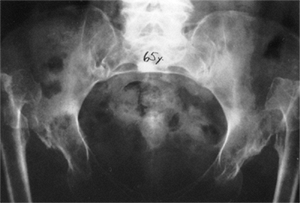

![]() |

Figure 24.9 A:

An 18-month-old girl with bilateral high dislocations. Note the poorly developed acetabula with well-developed secondary acetabula. B: At 33 months of age, the irregular ossification centers in the left and right hip have coalesced, with a slight improvement in the acetabular index. C: When the girl is 7 years of age, an anteroposterior view shows the appearance of the accessory centers of ossification in the periphery of the acetabulum. D: The accessory centers of ossification are somewhat better appreciated in the abduction view at 7 years of age. E: An anteroposterior view at 8 years of age shows the coalescence of the accessory centers of ossification, increasing the depth of the acetabulum. Note the excellent sourcil formation. F: The accessory centers of ossification are well demonstrated in an abduction view at 8 years of age. |